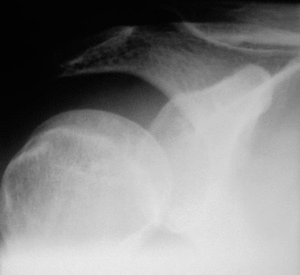

Las causas extrínsecas del atrapamiento del espacio subacromial se deben a anomalías en la bóveda acromial y a la articulación acromioclavicular. Bigliani y Morrison4 describieron en cadáveres tres tipos de acromion: el tipo I o plano, el tipo II o curvo y el III o en forma de gancho. Sólo el 39% de las articulaciones analizadas presentaron un acromion tipo III, si bien el 70% de éstos presentaban una lesión del manguito rotador (fig. 2). Por su parte, Gerber et al10 relacionaron el síndrome subacromial crónico con el atrapamiento subcoracoideo en relación con el papel de la apófisis coracoides y en sus tres formas, idiopática, yatrogénica y traumática.

Figura 2. Correlación radiográfica y de resonancia magnética (RM) de un acromion tipo III.